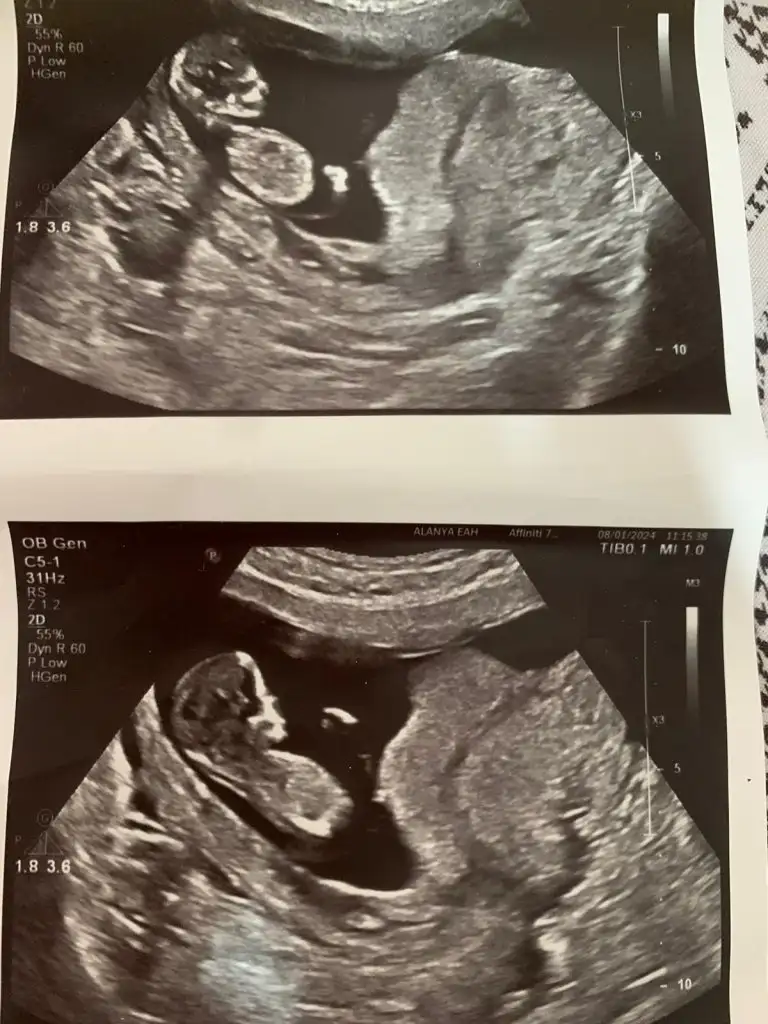

Canim banada tahminde bulunabilirmisin rica etsem.12+4 vaginal.Selam Kızlarbir çok kişi gruplardan beni bilir. Yine yetiştim imdatlara

5 ve 14. haftaya kadar olan ultrason fotolarınızı paylaşın. Vajinadan mı yoksa karından mı çekildiğini ve kaç haftalık olduğunu da mutlaka belirtin.